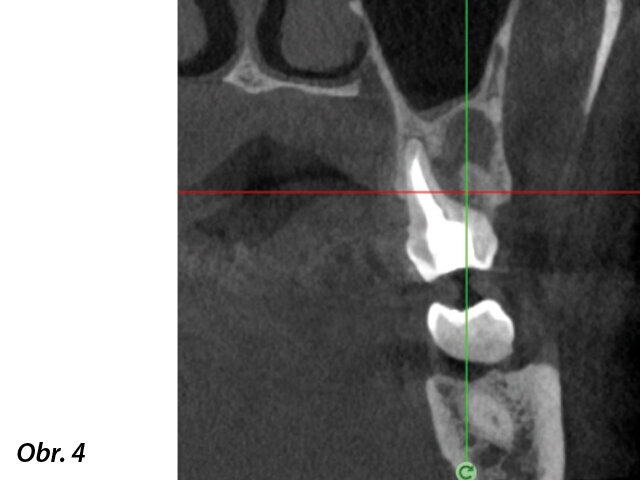

Klinický případ, kterým dále uvádím, je skvělým příkladem toho, jak obtížné je určit původ pacientových symptomů pouze na základě intraorálního snímku. Vizualizace 2D snímku selhává v jistotě určení přítomnosti léze, ještě důležitější však je, že je nemožné určit velikost, morfologii a typ léze, kterou se podaří nalézt. Analýza 3D snímku nám poskytne jasnou představu o klinické situaci: koronální a sagitální řezy odhalily přítomnost veliké léze sahající od apexu meziálního kořene tohoto moláru do furkace, zatímco axiální řezy nám umožňují provést přesnou analýzu endodontické anatomie a obzvláště pak tvaru meziálního kořene, který byl v tomto případě spojen s palatinálním kořenem. Celkový přehled o situaci ovlivňuje rozhodování o postupu a stanovení léčebného plánu zahrnujícího speciální úkony (obr. 1–4).